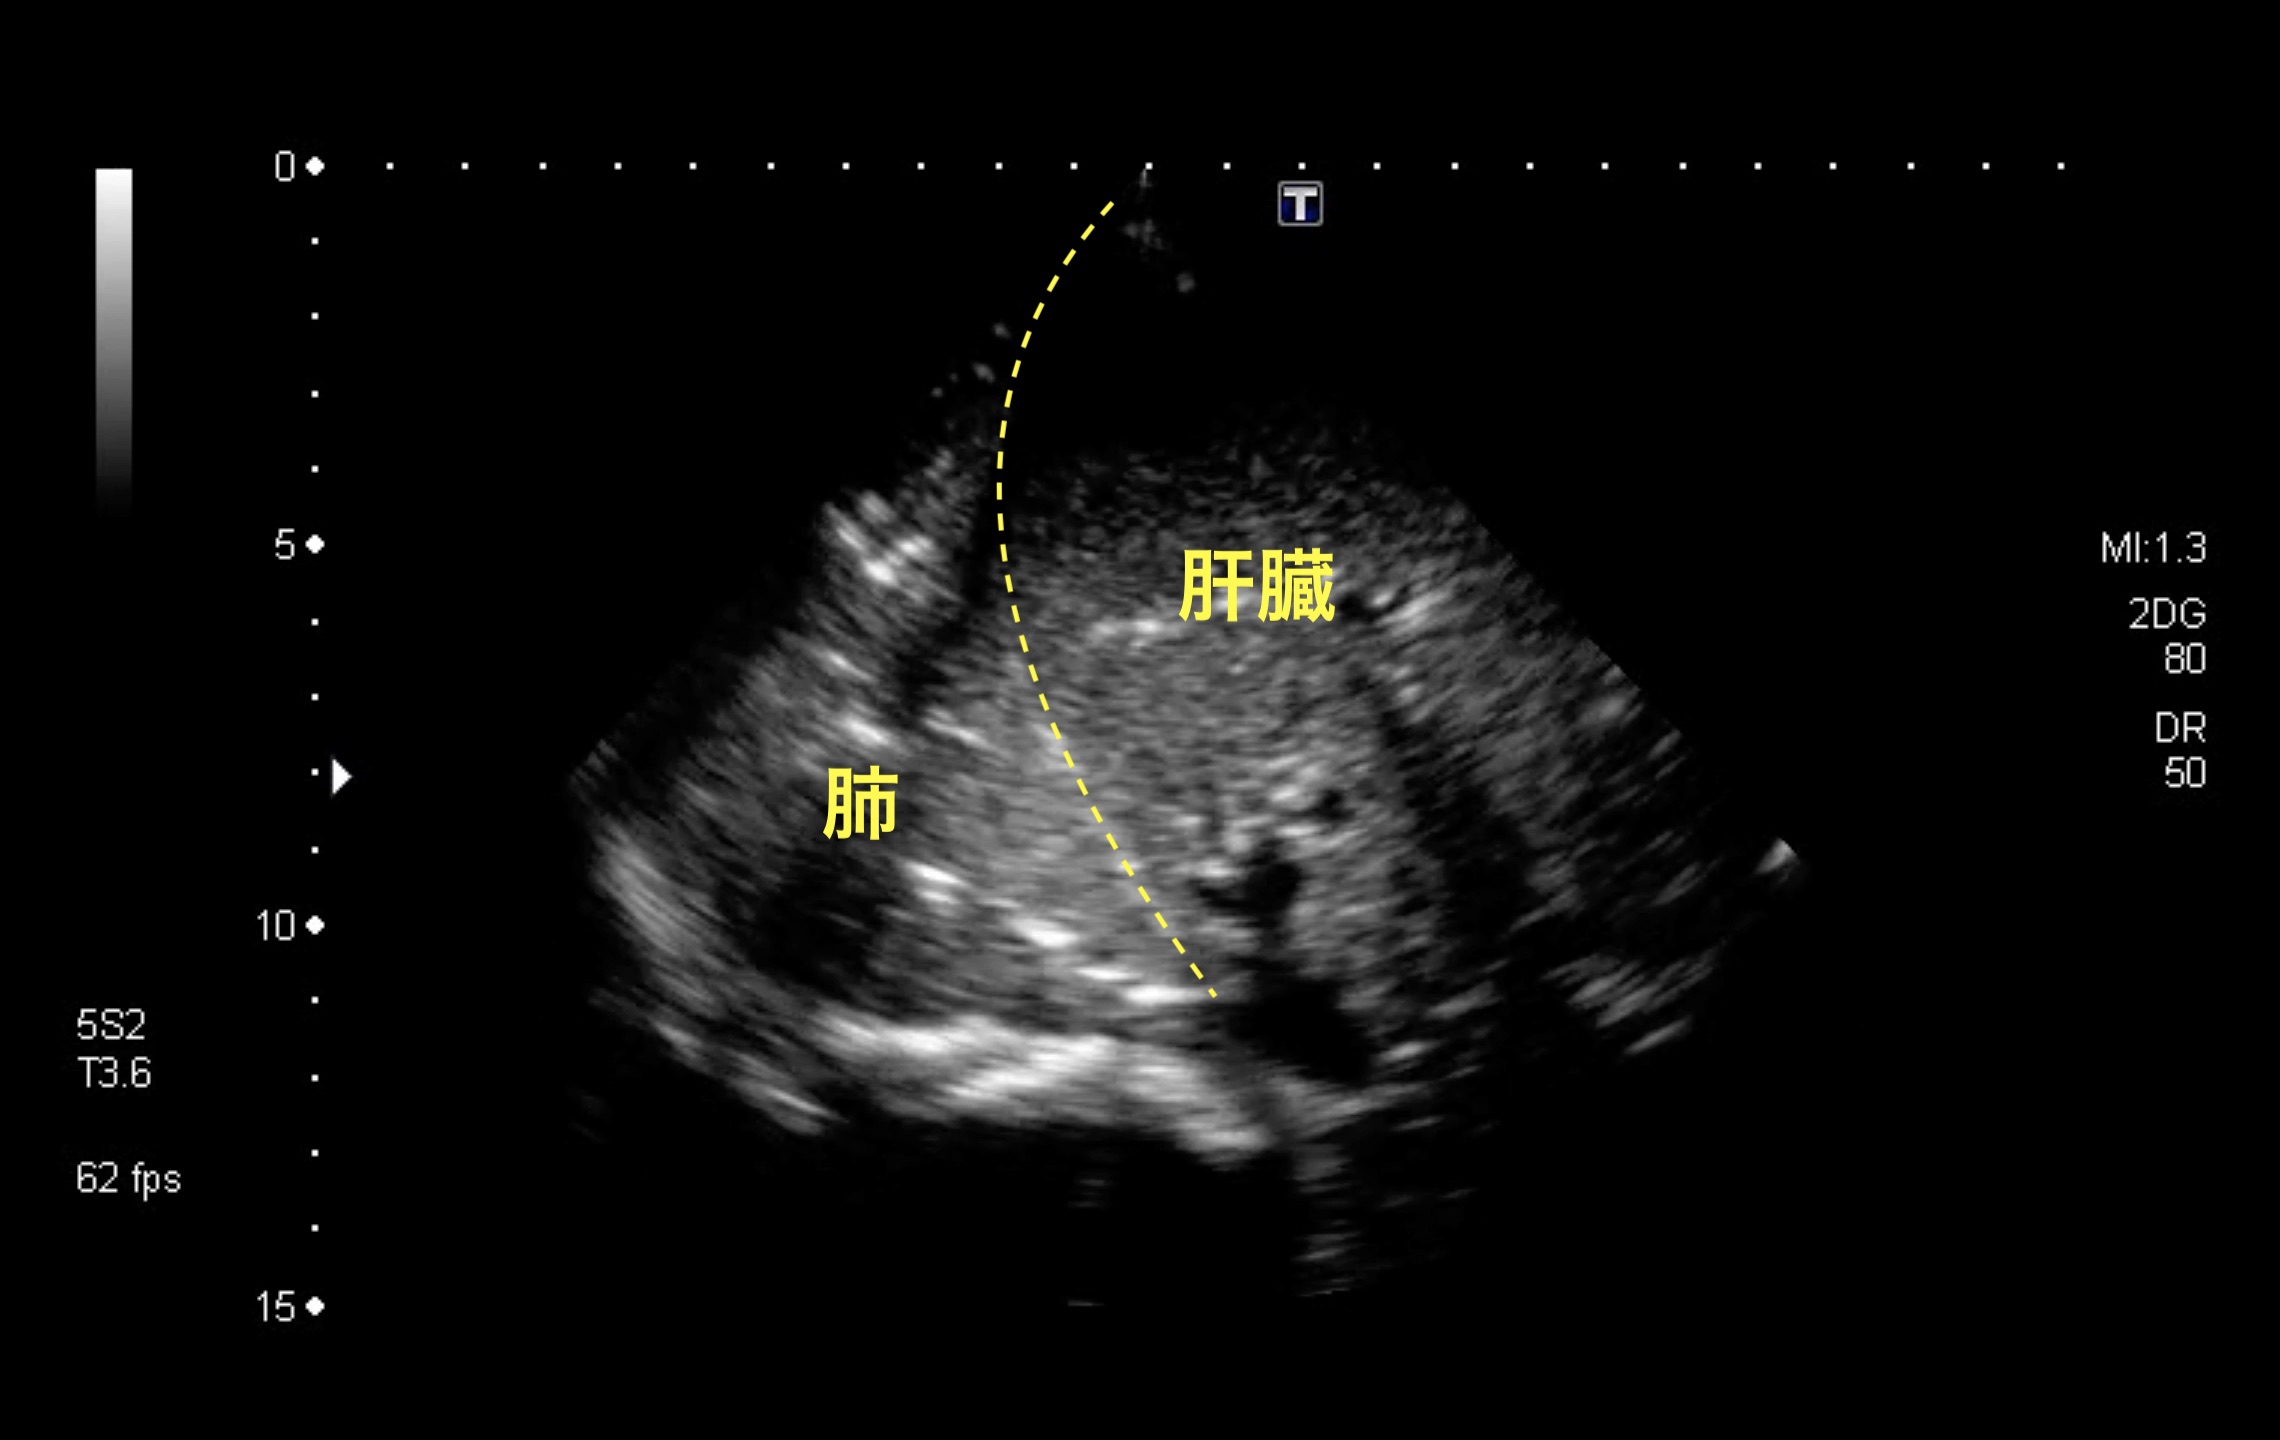

救急外来。発熱、呼吸困難。考えられる疾患はなにか。

肺炎、無気肺

健常者の肺は豊富な含気のためエコーにより肺の構造そのものを描出することはできないが、肺炎などで肺の含気が少なくなると、肺も他の実質臓器と同様にその構造物がエコーで描出可能となる。上の画像では、横隔膜を境に左右に類似した構造物が描出されているが、頭側(画面左)は肺、尾側は肝臓である。このように肺が肝臓と似た構造物として描出される状態は「Hepatization」とよばれる。無気肺単独でも類似の所見は生じるが、発熱などの感染徴候からは肺炎の存在が示唆される。